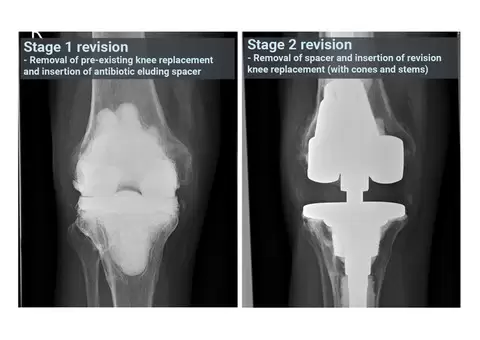

While the journey to mobility can be challenging, revision knee replacement offers hope for renewed freedom. This advanced procedure addresses complications from previous surgeries and restores function with precision and care.